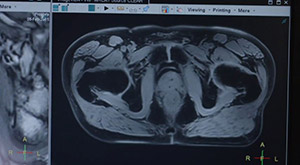

Today's challenging healthcare environment demands that you find new ways to drive clinical performance, enhance the patient experience and deliver economic value for your institution. We tackle these challenges with innovative tools and technologies, such as smart automation and MR-only simulation, to help you improve prostate cancer treatment planning and contribute to better outcomes for the patient.